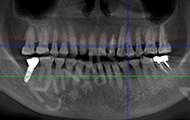

2018年4月3号 第一次来麦芽拍片

我很信任郑教授带领的种牙团队,而且现在不比当年了,科技也发达了,尤其是麦芽口腔的环境、设备、服务这些都感觉很高大尚,拍个片子都是三维的,不到10分钟,片子就呈现在医生的电脑上了,在几十年前哪有这种设备啊。

郑院长带领的医师团队,给我讲片子很清楚,说我的左上2牙齿出现松动,但是牙龈状况良好,可以告诉我牙齿即拔即种,无需等待3个月拔牙愈合期,避免二次创伤性伤口,他们以修复为导向,尤其我这种前牙的,还要兼顾咀嚼的咬合功能与美观性,虽然不太懂这个技术,但我还是很信赖郑院长的团队的,也感叹现在技术的先进。方案定制完成后,3D口扫取模,就跟牙刷大小一样的东西在口内扫一下,为了制定导板,种牙的时候更方便。